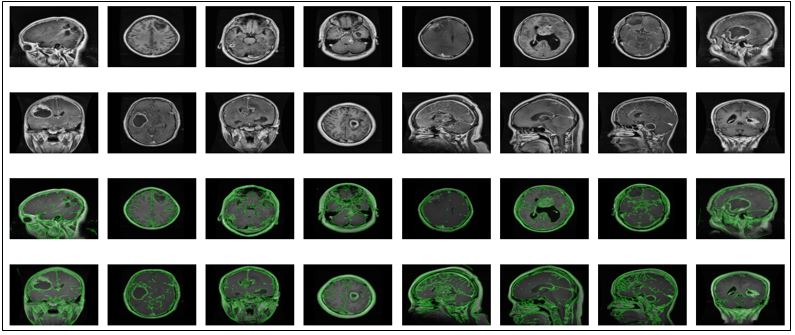

Enhanced Brain Tumor Diagnosis with EfficientNetB6: Leveraging Transfer Learning and Edge Detection Techniques

Adnan Hameed, Arsalan Khan, Sohail Ahmad, Sibghat Ullah, Abdul Nasir Khan, Sadiq Nawaz Khan

796-807